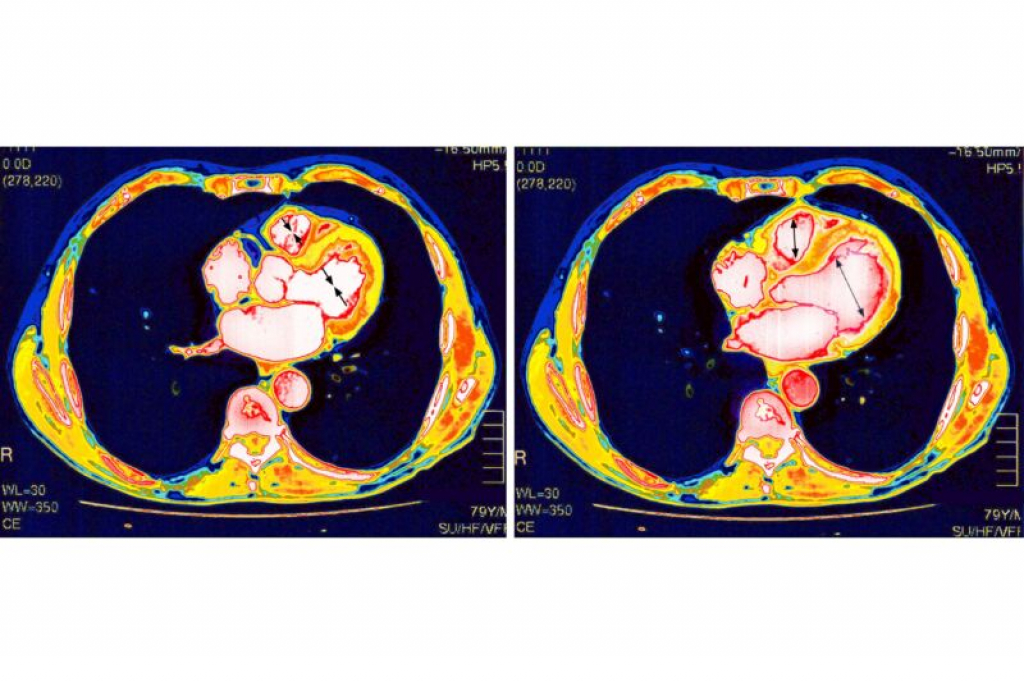

Recently, a collaborative study conducted by researchers from Northwestern University and the University of Michigan has come to the conclusion that a rare type of myocarditis (inflammation of the heart) is not caused by the COVID-19 vaccines.

This conclusion was reached after the researchers conducted a study with 15 female participants from both universities, who had been diagnosed with post-vaccine myocarditis between January and March of 2021. The participants had all received the Moderna and/or Pfizer vaccines.

The researchers sought to answer the question: Is myocarditis caused by the COVID-19 vaccines or by other factors? By examining previously collected data on the patients, such as their demographics and vaccine dosage, the researchers quickly ruled out the possibility that their condition was related to the vaccines.

Instead, they found that other underlying health conditions, predominantly comprised of cardiomyopathy, lupus and diabetes, may have been the cause of their myocarditis. Furthermore, the researchers uncovered that multiple infections with different viruses, such as the influenza virus, may have been at least somewhat responsible for the condition.